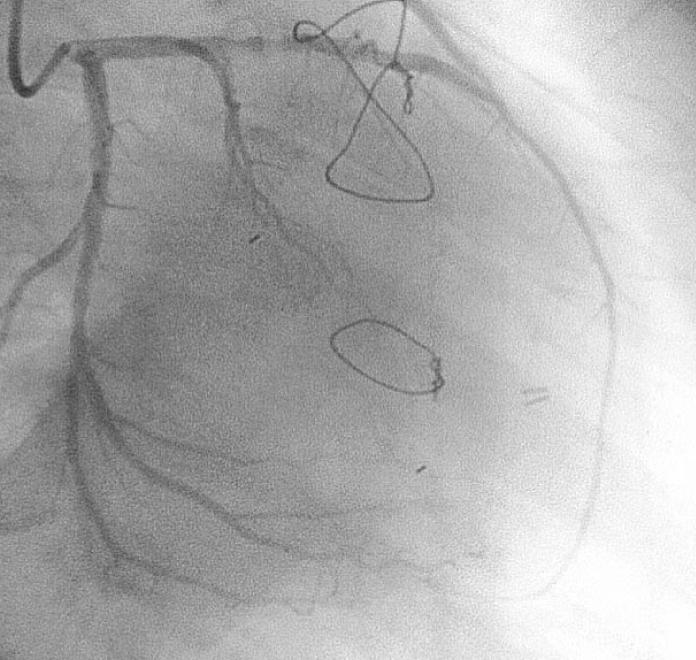

Coronary-subclavian steal through the left internal mammary graft is a rare cause of myocardial ischemia in patients who have had a coronary bypass surgery. We report a 70-year-old man who presented with sustained monomorphic ventricular tachycardia 5 years after the surgical creation of a left internal mammary to the left anterior descending artery. Cardiac catheterization illustrated that the left subclavian artery was occluded proximally and that the distal course was visualized by retrograde filling through the left internal mammary graft. Clinical ventricular tachycardia was reproducibly induced with a single ventricular extrastimulus, and antitachycardia pacing terminated the tachycardia. Restoration of blood flow by way of a Dacron graft placed between the descending aorta and the subclavian artery resulted in the total relief of symptoms. Ventricular tachycardia could not be induced during the control electrophysiologic study after surgical revascularization.

左内乳动脉桥至左前降支术后 5 年,1 例患者发生左锁骨下动脉近段闭塞,引起心肌缺血,导致持续性单形性室性心动过速,该患者为冠状动脉旁路移植术后少见的左内乳动脉窃血综合征。冠状动脉造影显示左锁骨下动脉近段闭塞,左内乳动脉桥通过逆行充盈显影。心外膜电生理检查时,单个心室早搏能诱发临床室性心动过速,抗心动过速起搏能终止心动过速。在降主动脉和锁骨下动脉之间放置涤纶移植物恢复血流,症状完全缓解。再次行冠状动脉旁路移植术后电生理检查时,室性心动过速不能诱发。